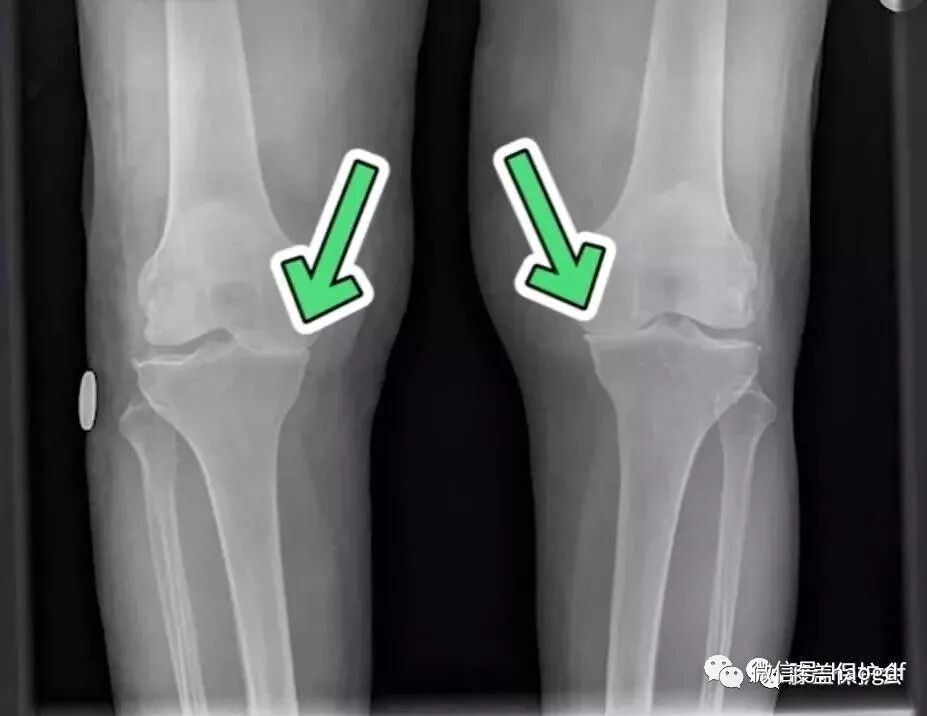

膝盖变形

有很多人膝盖原本是很直的,但当年纪慢慢变大后,腿形变成了O形腿。

这个问题,其实就是膝盖退化所造成的。我们的膝盖在磨损的时候,内侧的半月板会磨损的比较快。

当内侧半月板变得比较窄外侧比较宽,也就是整个腿形向内凹下去的感觉,就变成O形腿了。

另外这个膝盖变形的征兆还会附加一条,内侧变得比较肿胀。甚至有些人会一边膝盖有退化,另一边没有退化,你会发现有退化的那个膝盖是有很明显的肿胀的。

这个问题通常是它在变形的过程中,导致周围的韧带还有肌腱发炎比较严重,所以它也跟着发炎到肿胀。